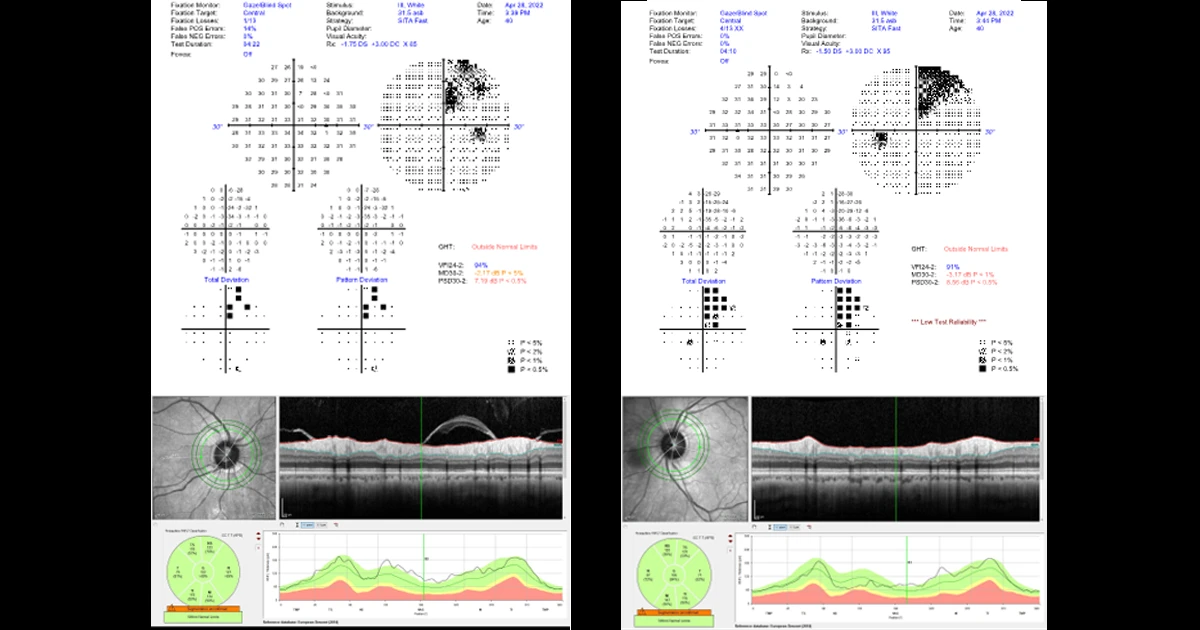

A 44 year old right handed male presented for a routine eye examination.

On questioning, he had been experiencing increasing headaches for the past 2 months. He had two headaches in total which presented as follows;

- blurred vision followed by headache

- can’t see anything on right hand side, aura for 30 mins, headaches lasted ½ day, always on right side

- persistent visual field loss post migraine

- some short-term memory loss

The patient has L occipital arteriovenous malformation (AVM). Stereotactic radiosurgery was performed with good results. The patient still experiences migraine headaches but without aura. He also has a persistent visual field defect due to scarring from AVM.